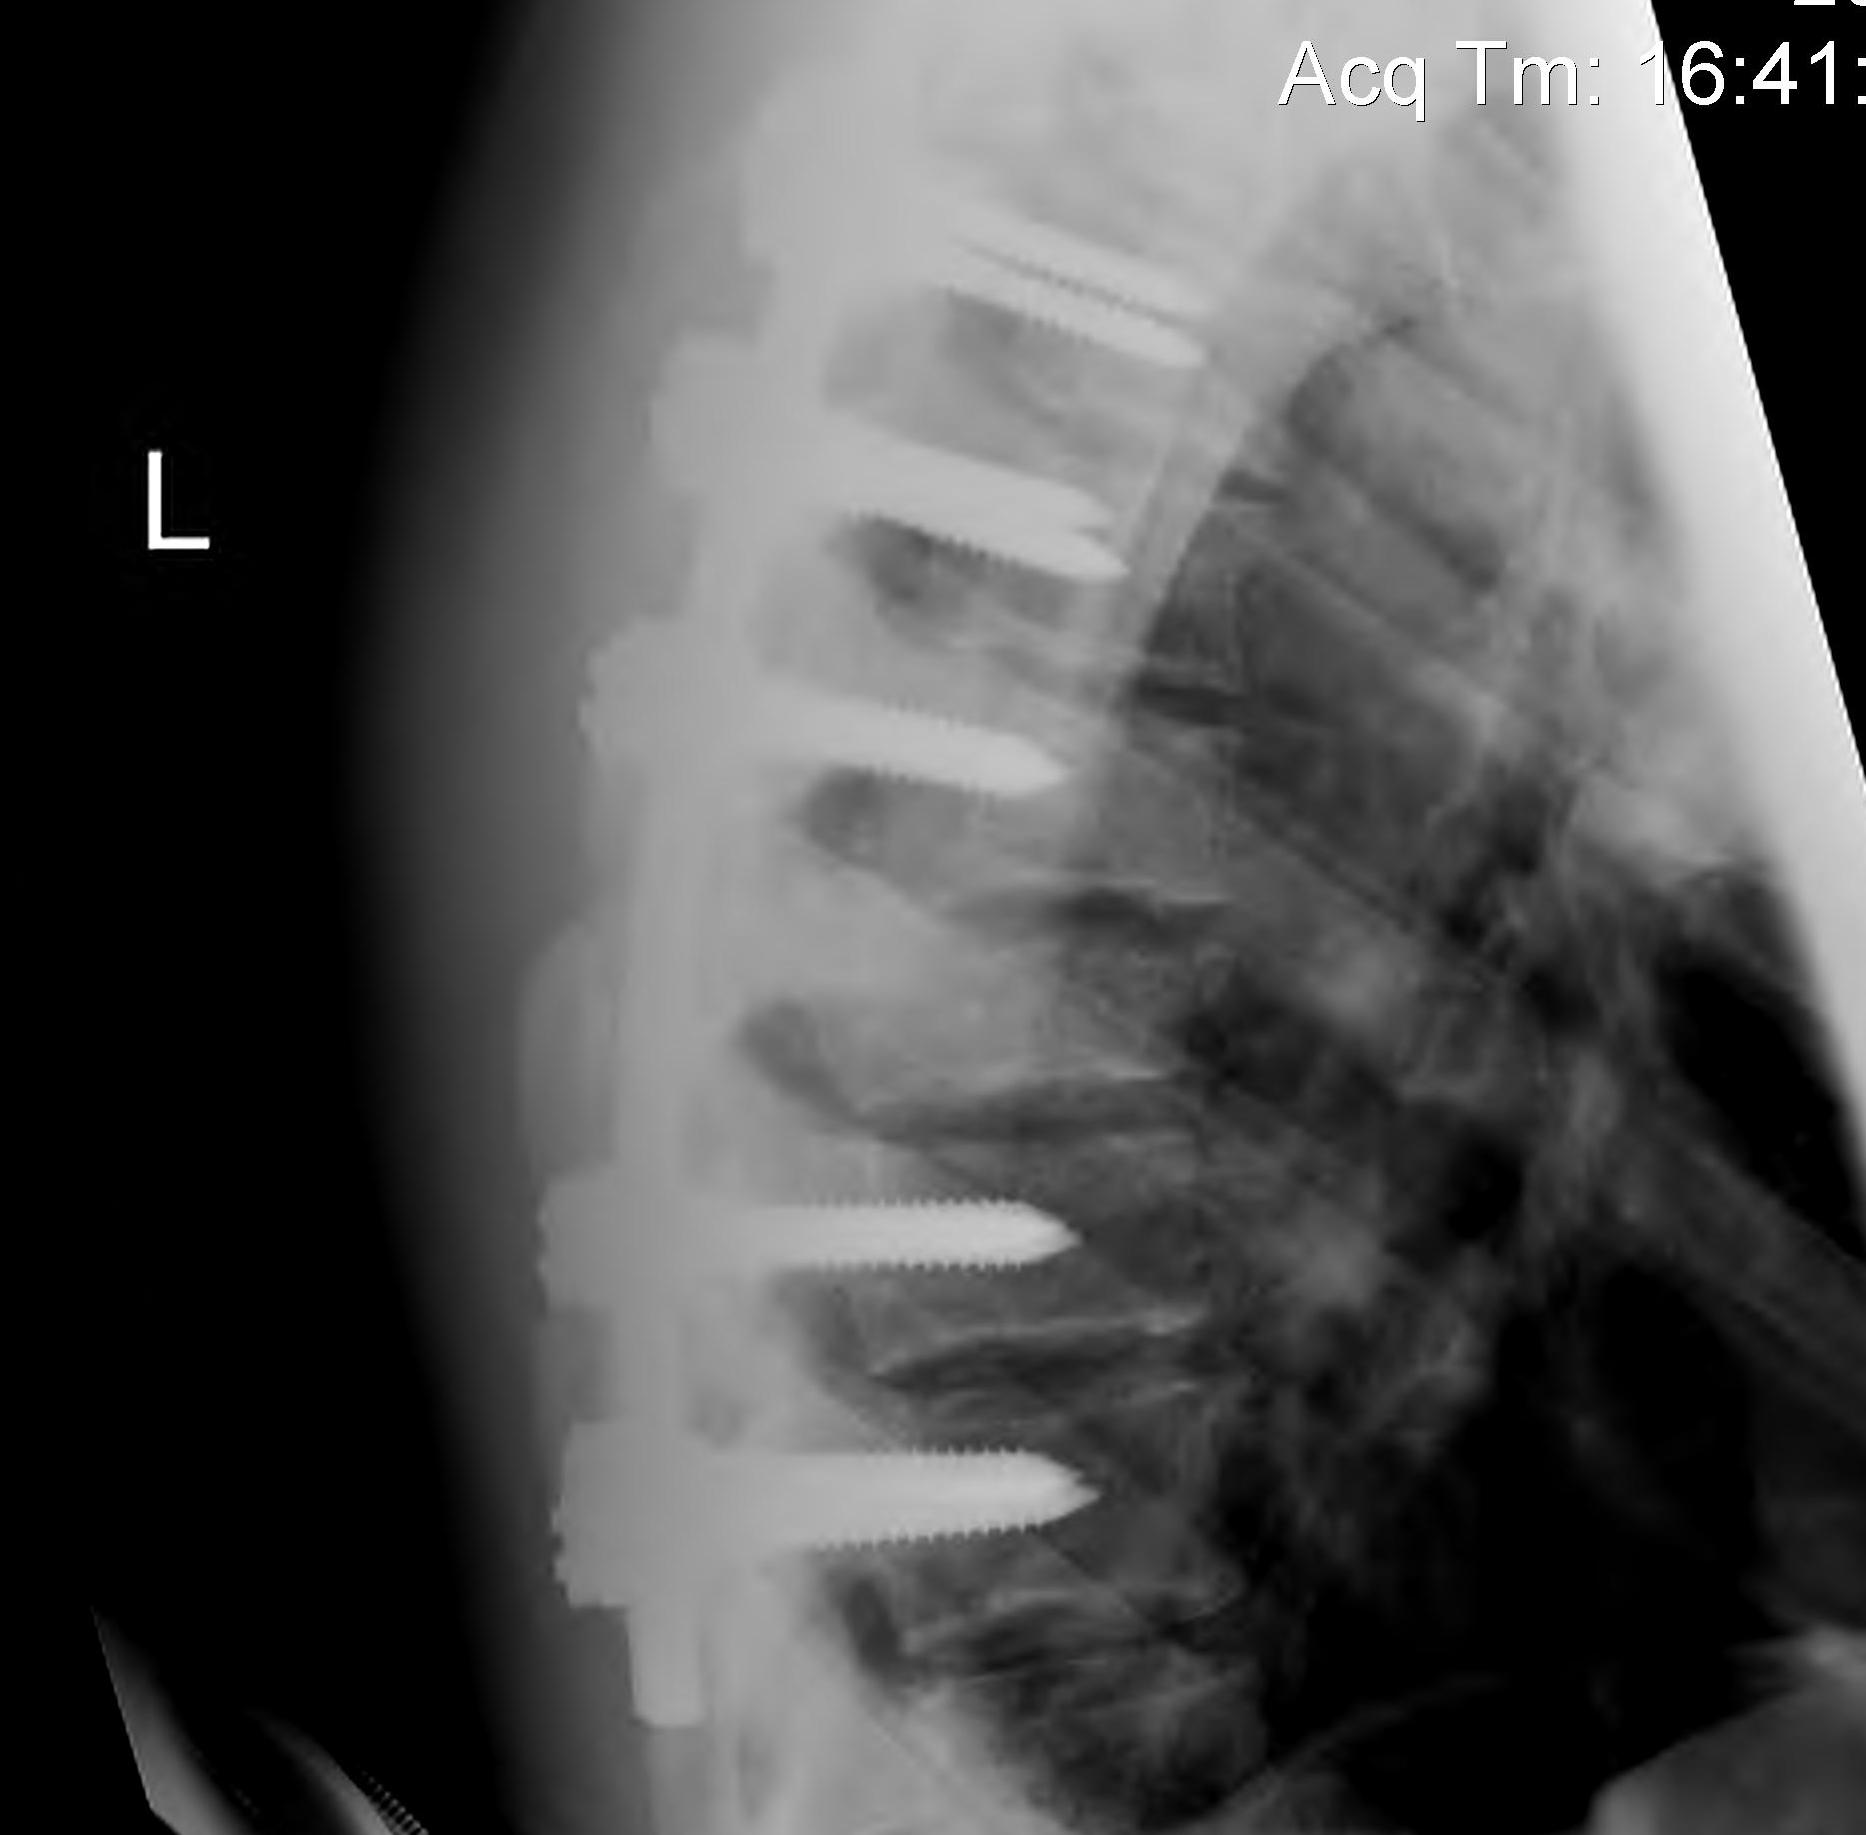

2. Burst Fracture

Characteristics

- axial load

- most common thoracolumbar junction

- retropulsed fragment here causes conus

CT

Look for canal compromise

- cord signal change

- kyphotic deformity

Retropulsed fragments

- always between pedicles

- typically one or two main fragments (saloon door)

- assess canal compromise